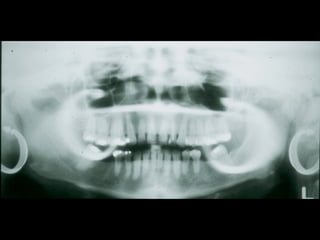

2. Các mốc giải phẫu trên phim toàn cảnh

1. Xoang hàm

2. Hố chân bướm hàm

3. Xương chân bướm

4. Gai bướm

5. Cung xương gò má

6. Lồi khớp xương thái dương

7. Đường khớp gò má thái dương

8. Mỏm gò má

9. Lỗ ống tai ngoài

10. Mỏm chũm

11. Hố sọ giữa

12. Bờ viền ngoài ổ mắt

13. Bờ dưới ổ mắt

14. Lỗ dưới ổ mắt

15. Ống dưới ổ mắt

16. Hốc mũi

17. Vách ngăn mũi

18. Gai mũi trước

19. Xương cuốn dưới

20. Lỗ răng cửa

21. Vòm miệng cứng

22. LồI củ xương hàm trên

23. LồI cầu

24. Mỏm vẹt

25. Khuyết sigma

26. Hố giữa khuyết sigma

27. Mỏm trâm

28. Cột sống cổ

29. Gờ chéo ngoài

30. Ống răng dưới

31. Lỗ ống răng dưới

32. Gai Spix

33. Lỗ cằm

34. Hố tuyến dưới hàm

35. Gờ chéo trong

36. Hố cằm

37. Gờ cằm

38. Gai cằm

39. Xương móng

40. Lưỡi

41. Vòm miệng mềm

42. Lưỡi gà

43. Thành sau họng

44. Dái tai

45. Khoang lưỡi hầu

46. Khoang mũi hầu

47. Khoang vòm miệng lưỡi